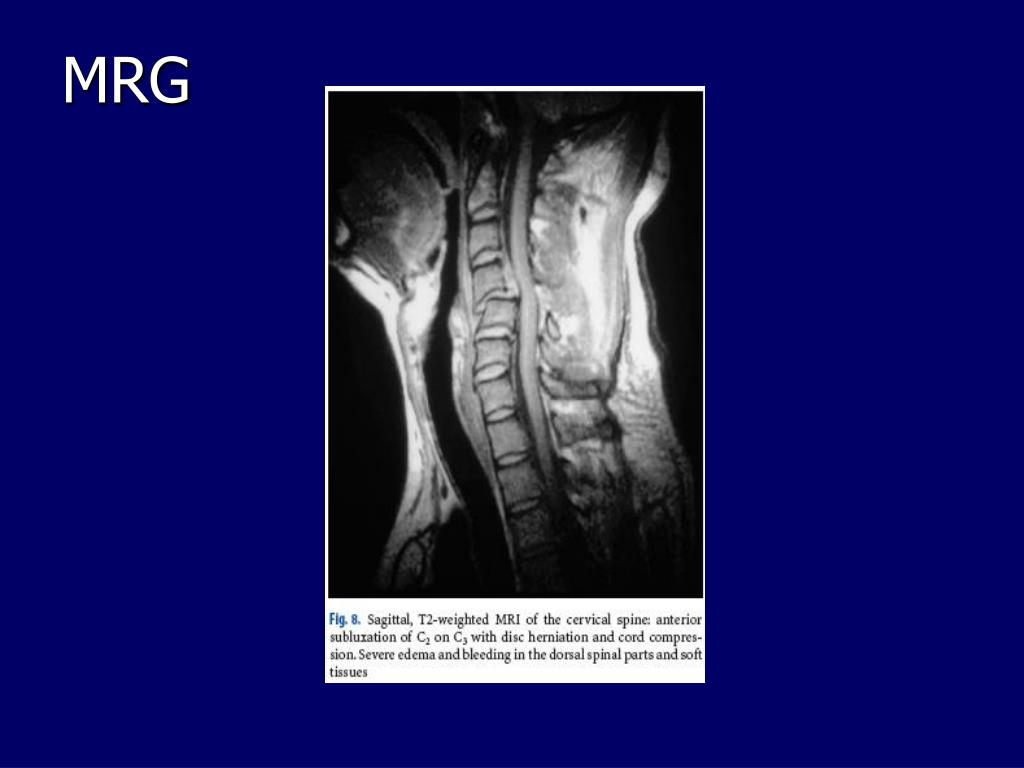

21. C5-6 dislokasyon